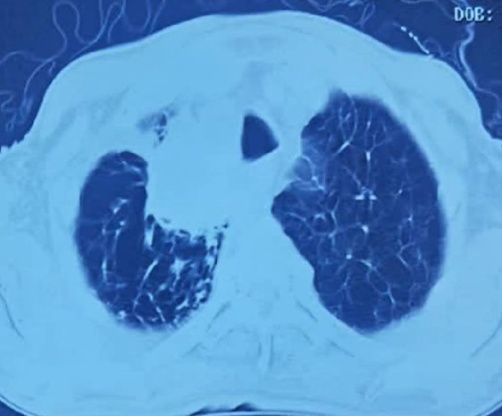

患者入院后一般状况尚可,但胸部CT片确实很令人吃惊,肺的状态很差,至少50年以上烟龄,病灶不小,位于右肺上叶近纵隔,穿刺风险巨大,还有气胸风险。为了早日得到明确诊断早日治疗以消除家属的焦虑,且不辜负患者和家属的信任,肿瘤科医护于住院当天下午立即为患者做了CT导航下肺肿物穿刺活检术。

活检中图像